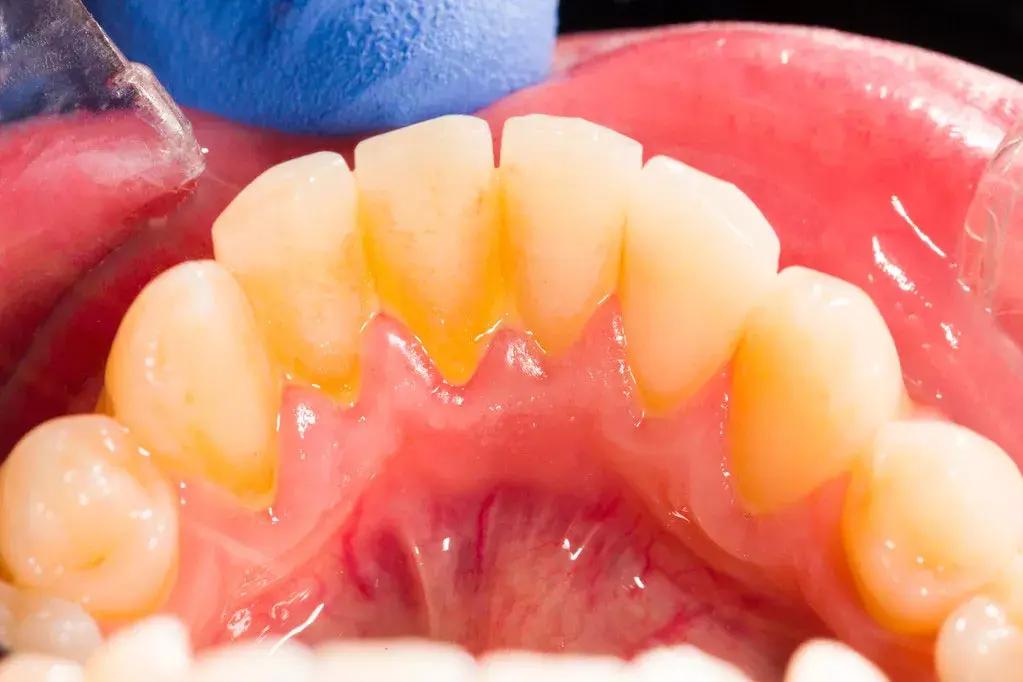

为了不张嘴就像西红柿炒蛋,很多小伙伴每天刷牙,几乎从无间断。可仔细看镜子时也会发现:牙齿内侧还是会有 黄色 甚至 棕黄色 的东西……

2、硬化、抠不掉的

而已经发硬、抠不掉的黄色物质就是 牙石 ,它是长期滞留的菌斑、软垢与唾液中的矿物质结合后,逐渐钙化形成的。如果有吸烟的习惯,它还会被着色变成棕色,甚至黑色。

牙石的形成就像滚雪球一样:菌斑矿化后形成的粗糙表面为细菌安家提供了便利,新的菌斑沉积又矿化……牙石越变越厚,它的表面总有“新鲜”的菌斑在猖獗,而它本身也是多孔的,更加利于藏污纳垢。此外,其吸附的细菌毒素还会不断刺激它无辜的邻居——牙龈,甚至进一步侵犯我们的牙周组织。